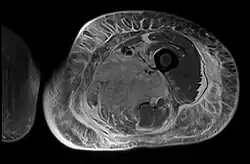

Axial fat suppressed T2 weighted MRI image showing hyperintense signal and enlargement of the left thigh adductor muscle group in diabetic myonecrosis.

Creatine kinase may be normal or increased probably depending upon the stage of the condition when sampling is undertaken. ESR is elevated. Planar X-ray reveals soft tissue swelling and may potentially show gas within necrotic muscle, Bone scan may show non specific uptake later in the course. CT shows muscle oedema with preserved tissue planes (non-contrast enhancing). MRI is the exam of choice and shows increased signal on T2 weighted images within areas of muscle oedema. Contrast enhancement is helpful but must be weighed against the risk of Nephrogenic Systemic Fibrosis as many diabetics have underlying chronic kidney disease. Arteriography reveals large and medium vessel arteriosclerosis occasionally with dye within the area of tissue infarction. Electromyography shows non specific focal changes.